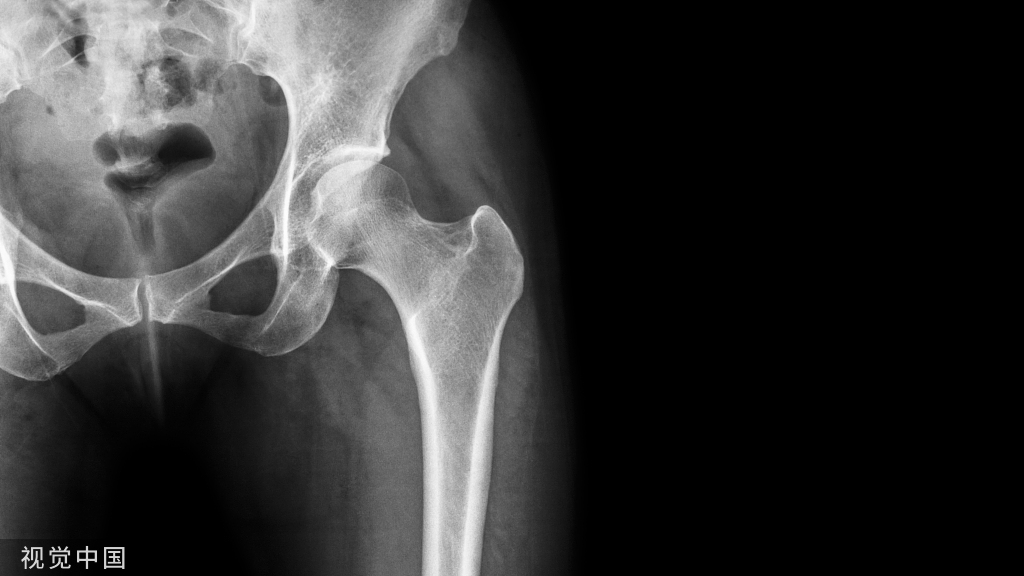

结果:回顾了22例舟状骨手术固定和9例舟状骨非手术治疗。手术组出现骨不连1例。舟状骨骨折的手术处理导致活动时间(2周复位)和放射愈合时间(8周复位)显著减少。

结论:本研究表明,手术治疗舟状骨骨折合并桡骨远端骨折可缩短X线愈合时间和临床活动时间。这表明手术治疗可以早日恢复运动,但保守治疗在舟状骨骨折和桡骨远端骨折愈合率方面与手术治疗没有统计学差异。